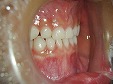

乳歯の前歯が抜ける6、7歳の時期に上下前歯の歯並びがデコボコしてきた場合は、床矯正(取り外し可能な矯正装置)・食育・咀嚼訓練などを行い口腔周囲筋・咀嚼系筋群を活性させ正常な顎骨に発育させることで歯のデコボコを治していきます。床矯正を始める年齢・永久歯の萠出状態によりワイヤーによる歯列矯正も必要になる場合があります。

受け口(反対咬合)治療は3歳ぐらいから治療可能です。当医院ではパナシールドやムーシールドなどを用いて治療を開始します。

◆床矯正

◆床矯正反対咬合